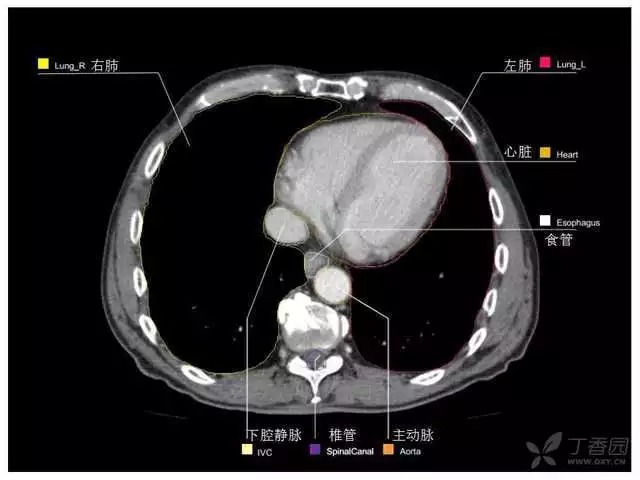

腹部肝脏高清CT断层的图谱

全腹部高清CT图谱,淋巴结彩色图谱,血管解剖图谱大汇总!

超声肝脏分叶及分段

肝脏分段和基本解剖学标志